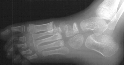

Radiographs of the patient were obtained on her presentation to our clinic. These confirmed the finding of increased radiodensity of the navicular with a flattened appearance to the ossific nucleus. Furthermore they revealed increased density and callus formation in the proximal 1st through 4th metatarsals. This was consistent with multiple non-displaced fractures of the proximal metatarsals secondary to trauma. While Kohler's disease cannot be ruled out in this case, it is more likely that the patient had symptoms produced by her metatarsal fractures. The radiographic appearance of the tarsal navicular almost certainly preceded the acute traumatic event. Therefore, she probably had metatarsal fractures superimposed on irregular ossification of the tarsal navicular giving a clinical picture similar to Kohler's disease.